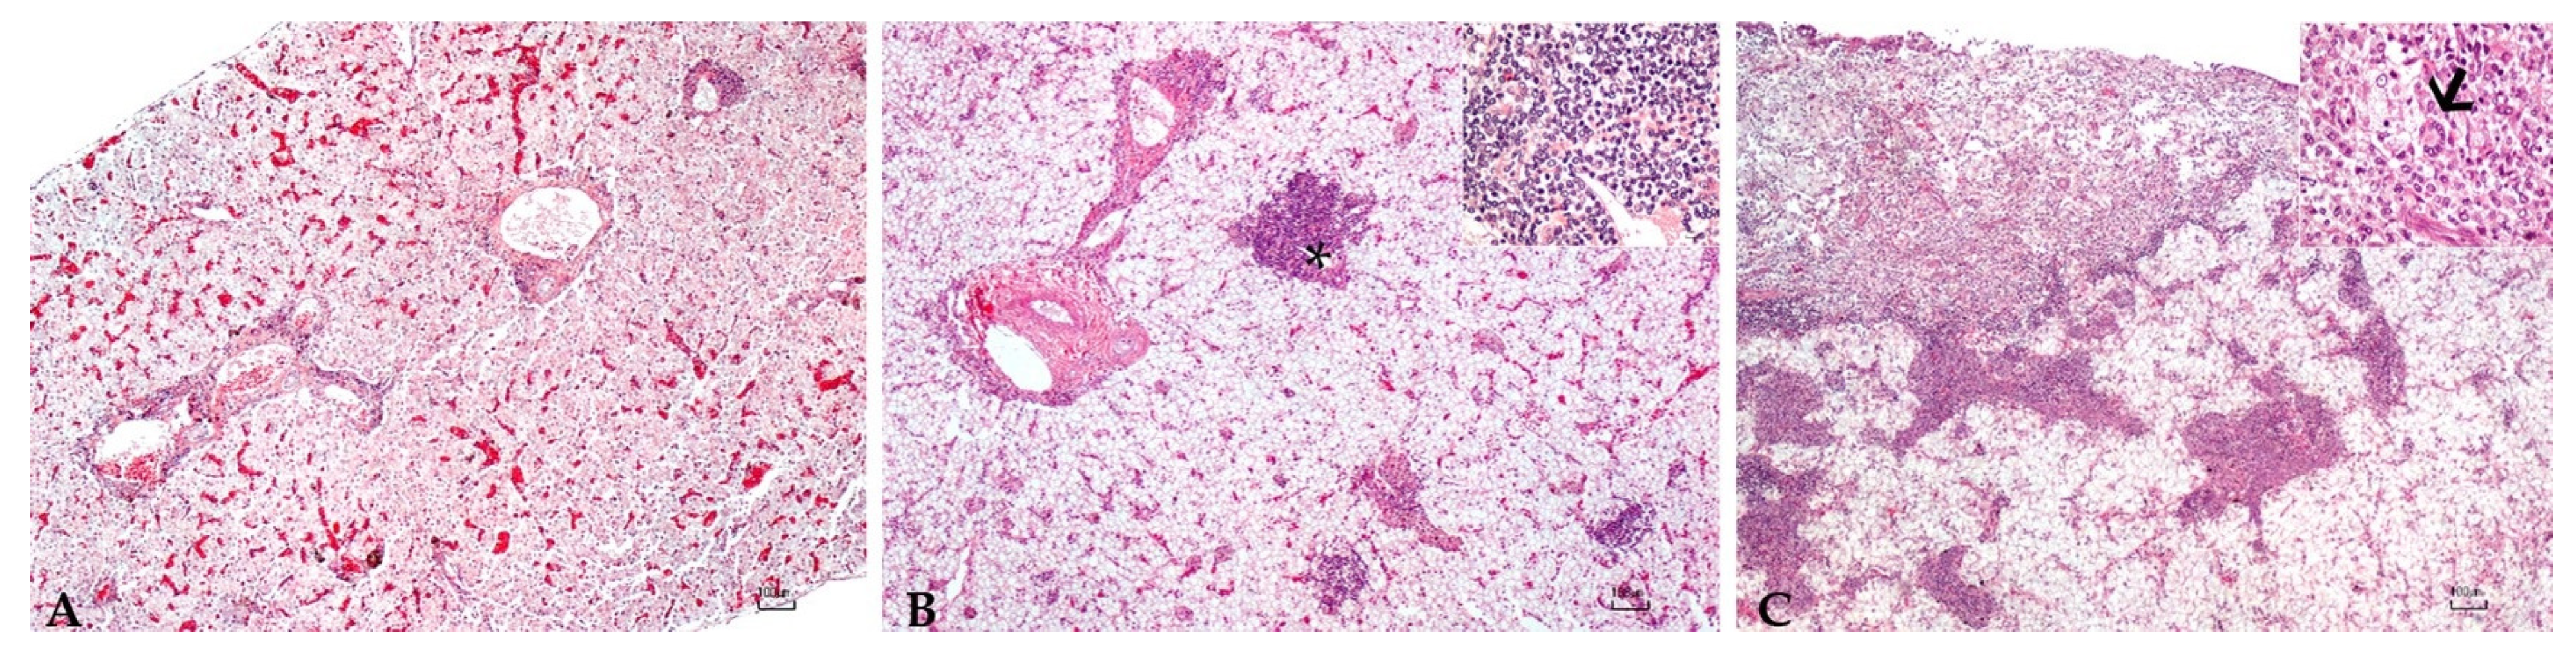

Sturgeons showed mild to severe granulomatous chronic inflammatory reactions ranging from mild to severe degrees in all examined organs. In particular, the hepatic parenchyma was expanded by multifocal to coalescing, multinodular, variable size granulomas mainly located near vessels and bile ducts and extended to the serosal surface in the most severe cases (Figure 1). Mild and diffuse congestion of blood vessels was observed in a single case with mild inflammation. The spleen was diffusely expanded in all sturgeons except in one specimen, by a mild to severe chronic granulomatous inflammation associated with edema and vascular congestion (Figure 2). In two out of four sturgeons, the serosa and the outer muscular layer of the small intestine were characterized by a diffuse granulomatous inflammation, whereas the mucosa and submucosa were unaffected (Figure 3). Results are summarized in Table 2.

Figure 1. Liver: Mild (A), moderate (B), and severe (C) granulomatous chronic hepatitis cantered around the bile ducts and arterial vessels (asterisk, (B)). Granulomas consisted of a high number of macrophages, a moderate number of lymphocytes and plasma cells, scattered eosinophilic granular cells (inset (B)), and occasionally 80–100 µm, round, multinucleated cells with round peripherally-located nuclei with dispersed chromatin and granular eosinophilic cytoplasm (Langhans-type cells) (arrow, inset (C)). H.E. Bar (AC) = 100 µm, inset 10 µm.

The previous paper of Mugetti et al. [28] showed clinical signs consistent with those ready reported regarding A. baerii [8] and A. transmontanus [25]. In this second episode two sturgeons were externally normal, even if the histopathological analysis reported a mild inflammation of the liver and the spleen; other two samples were instead characterized by starvation and skeletal deformities, as already reported for A. transmontanus [26]. Moreover, the multifocal involvement of the liver, spleen, and of the intestine mainly centered around vessels and bile ducts, indicating a systemic granulomatous inflammation, and was reported.

The multinucleated cells are noteworthy. Although seldom reported in the fish inflammatory response of bacterial origin, the specimens herein described were found in association with reactive macrophages. These results suggest that these cells in sturgeons could be part of granulomatous inflammation against bacteria.